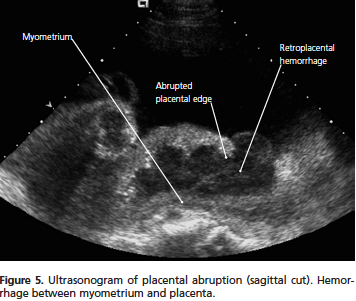

What is placental abruption?

the seperation of the placenta from the uterine wall before delivery

T. B/c ultrasound is not reliable in diagnosing abruption